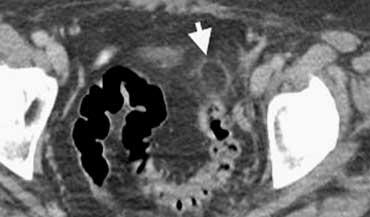

TRÁI: Viêm túi thừa sigma. Túi thừa (mũi tên) được bao quanh bởi lớp mỡ tăng tỷ trọng. Thành sigma dày. PHẢI: Ung thư sigma với dấu hiệu mờ mỡ giới hạn.